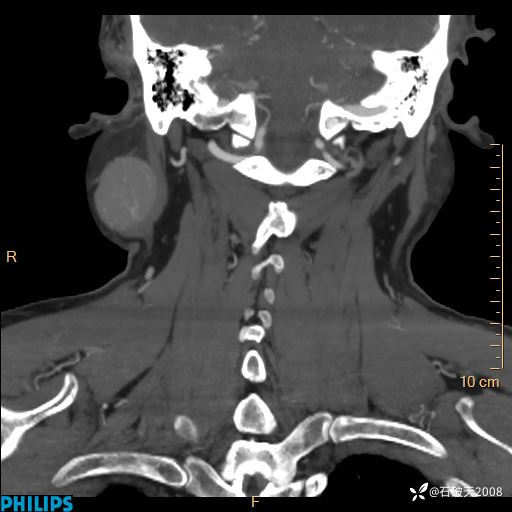

病例分享:颈部占位,一周后公布病理

男 57岁 主 诉:发现右侧颌下肿物1月余。

现病史:1月余前家属发现右侧颌下肿物。局部皮肤无红肿、热痛,无吞咽困难,无异物感,无恶心、呕吐,无头痛、头晕,无胸闷、胸痛,无发热、咳嗽、咳痰及呼吸困难。于我院行体表肿块彩超检查(2024.03.15我院)示:右侧耳下皮下软组织内低回声,未治疗。今为进一步治疗门诊以“腮腺肿瘤”为诊断收住我科,发病来患者神志清,精神可,饮食、睡眠及大小便正常,体重无明显下降。

平扫